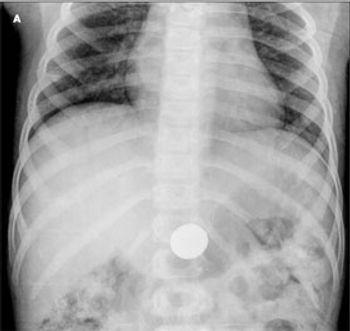

This rash erupted on the upper body of a 58-year-old woman in late August. It was mildly pruritic and nontender. The patient had not started any new medications and was not taking photosensitizing drugs. She had Sjögren syndrome; the rest of her history was noncontributory. Subacute cutaneous lupus erythematosus (SCLE) was diagnosed. SCLE typically affects white women aged 30 to 40 years.1 It presents as nonindurated, nonscarring, erythematous plaques with or without a fine scale that may progress into a diffuse, widespread, papulosquamous or annular lesion with central hypopigmentation or telangiectasia.